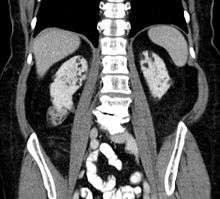

Between 60 and 80% of tuberous sclerosis patients have benign tumors (once thought hamartomatous, but now considered true neoplasms) of the kidneys called angiomyolipomas (AML) frequently causing hematuria. These tumors are composed of vascular (angio–), smooth muscle (–myo–), and fat (–lip-) tissue. Although benign, an angiomyolipoma larger than 4 cm is at risk for a potentially catastrophic hemorrhage either spontaneously or with minimal trauma. Angiomyolipomas are found in about one in 300 people without tuberous sclerosis. However, those are usually solitary, whereas in tuberous sclerosis they are commonly multiple and bilateral.

About 20-30% of people with tuberous sclerosis have renal cysts, causing few problems. However, 2% may also have autosomal dominant polycystic kidney disease.

Very rare (< 1%) problems include renal cell carcinoma and oncocytomas (benign adenomatous hamartoma).